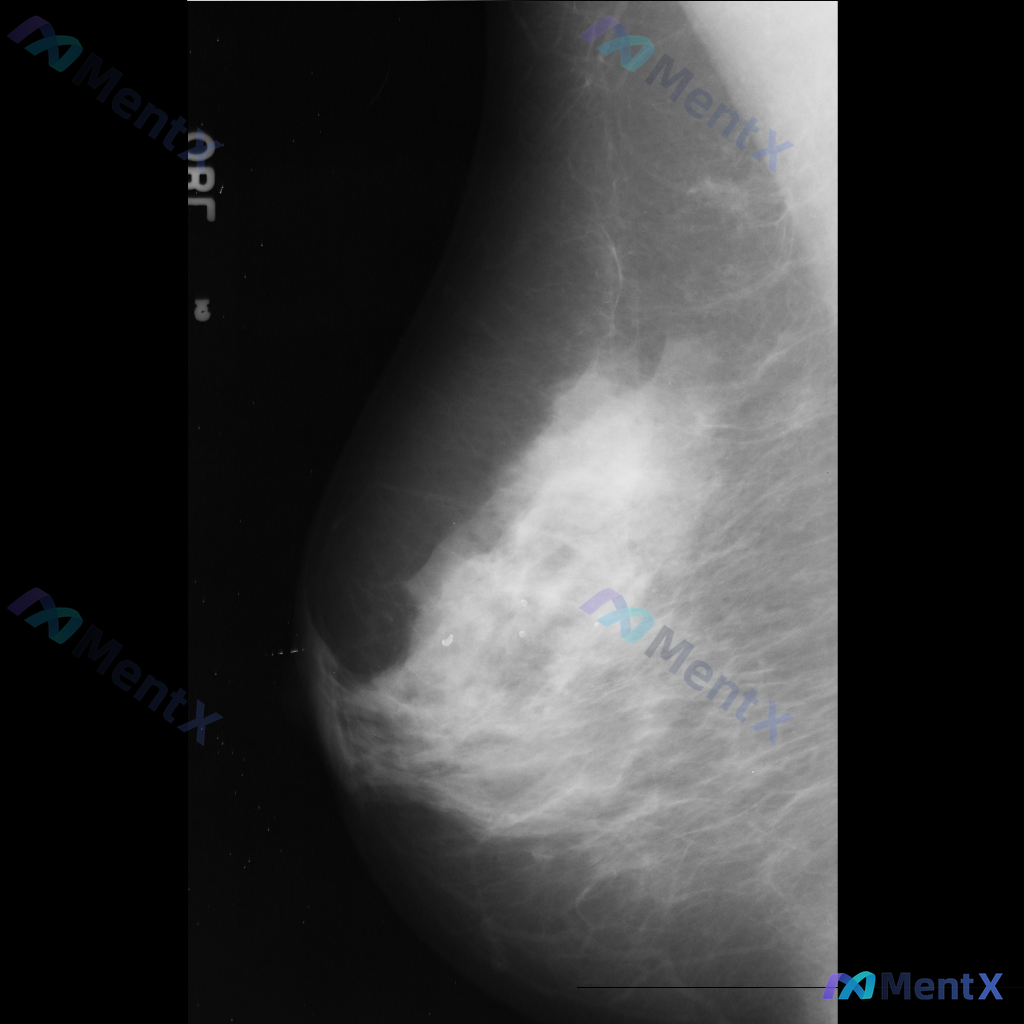

整理到一张乳腺钼靶影像资料,大家一起讨论下。 影像表现大概是这样: - 异常区域位于乳腺下象限偏外侧 - 可见一局限性致密影,形态大致呈卵圆形或不规则形 - 边缘部分清晰,局部可能模糊或有细微毛刺样改变 - 致密影密度高于周围脂肪组织,与纤维腺体组织密度相似或略高 - 周围乳腺小梁结构似有轻微的牵拉...

整理到一张乳腺钼靶影像资料,影像所见:左乳中上象限可见不规则高密度致密影,边界部分模糊或伴毛刺状改变,局部乳腺组织结构可见轻度扭曲。 想和大家讨论一下:单看这张影像的异常表现,你认为用哪个术语描述最贴切?